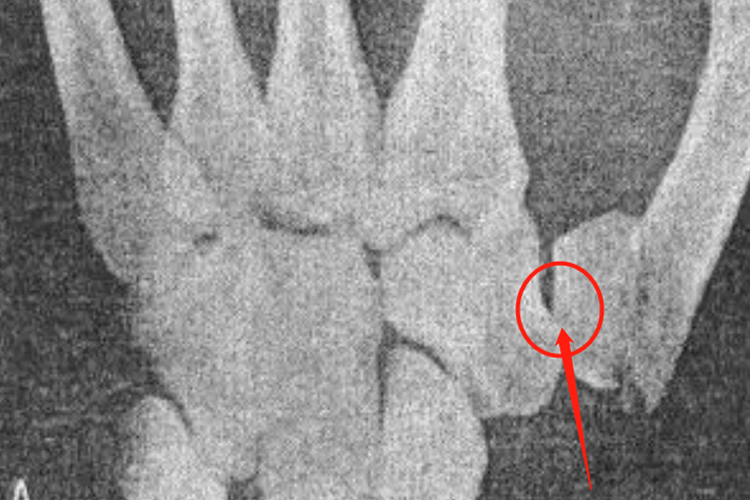

大多角骨骨折可出现腕关节桡侧肿胀、压痛、活动受限。舟骨结节处常有压痛,疼痛可沿拇展长肌腱放散。拇指活动可不受限,但拇指与其他指的捏力减弱。极少数掌侧缘骨折者可引起正中神经压迫症状。大多角骨骨X线可表现为纵向骨折线,三块以上的骨质块和压缩性骨折。

稳定型和撕脱大多角骨骨折可行石膏固定4周后,改用石膏夹板保护进行功能锻炼。对不稳定骨折、骨折线穿过大多角骨与掌骨之间关节的骨折,需行开放复位,螺钉或克氏针固定。如掌侧缘骨折不连接,也可经掌侧入路切除骨折片。